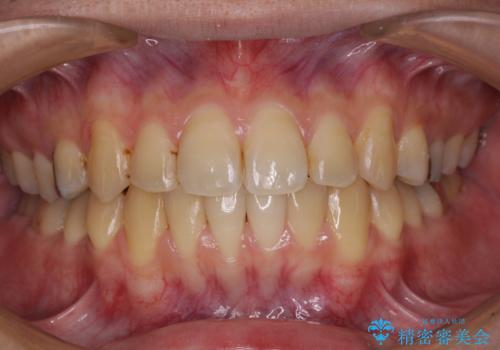

下顎の骨格的なズレが大きかったため、上下歯列のバランスが取れるか心配でしたが、上下ともに左右対称に近い歯列で治療を終えることができました。